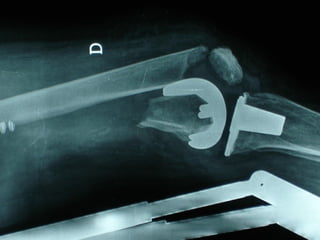

INDICAZIONI COMUNI Fratture sovracondiloidee Fratture intercondiliodee Fratture diafisarie distali PARTICOLARI Fratture con grave osteoporosi Fratture periprotesiche

VANTAGGI CHIRURGIA MININVASIVA Mini Open Inserimento della placca sottocutaneo per scivolamento Viti percutanee Preservazione dei tessuti molli Ridotto danno vascolare Rapida ripresa funzionale

F, 68 y

LISS  NCB

NCB

Conclusioni Riduzione  anatomica Minimo trauma chirurgico Corretto equilibrio fra elasticità e stabilità Precoce mobilizzazione